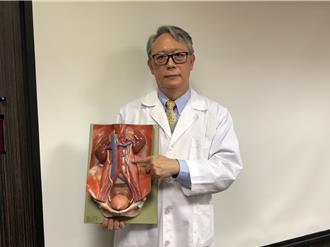

台北榮總新竹分院泌尿科團隊近日在體外震波碎石中心主任陳炫達的主導下,為一名長年飽受左腎結石與反覆感染之苦的患者,施行腹腔鏡左側腎臟切除術。手術過程順利,病人術後恢復良好,預期可大幅改善長期腰痛與感染的問題。

尿路結石是常見的泌尿疾病之一,屏東醫院泌尿科醫師張哲維表示,喝水不足是尿路結石首因,預防尿路結石的「五要點」,每日要攝取2500至3000c.c.水分、避免高鹽飲食減少高蛋白攝取、降低高普林與高草酸食物攝取、注意慢性病控制與家族史風險、曾罹患尿路結石者應定期追蹤。

柯文哲今輸尿管結石手術 醫示警:1情況腎臟只剩一層皮

反覆尿道感染 照出3顆大結石

反覆尿道感染,可能合併出現尿路結石!一名58歲楊小姐,多年來反覆泌尿道感染,近期因抗生素治療效果不佳,加上左腰痠痛數天而就醫,一照超音波,發現左側腎臟內有3顆近1公分大結石,且腎臟已呈現明顯腎盂、腎炎反應。

長期腰痠別輕忽!58歲婦反覆泌尿道感染 腎臟藏3顆大結石

一名58歲楊小姐,多年來反覆泌尿道感染,近期因抗生素治療效果不佳,加上左腰痠、脹數天而就醫,一照超音波,發現左側腎臟內有3顆近1公分大結石,且腎臟已呈現明顯腎盂、腎炎反應。

7旬男腹痛檢出4公分鹿角結石 醫給4建議防結石反覆發生

70歲的黃姓男子因腹部脹痛而至醫院就醫,經腹部超音波檢查發現左腎有結石,且有血尿的情況,進一步安排X光檢查,確認左腎有一個約4公分長、2公分寬的鹿角結石。比對三年多前的X光報告,當時尚未形成此結石,判斷是因細菌感染造成的「感染性腎結石」,才會讓結石如此快速長大。

46歲男腎結石頻復發慘血尿 醫1招成功保腎

46歲蘇先生年輕時出現腎結石,經過多次體外震波碎石治療,都無法完全清除、頻繁復發,近期因腰部疼痛,甚至出現血尿,趕緊到新光醫院就醫。與醫師討論後,決定採取「軟式輸尿管鏡手術」,有效清除腎結石。

77歲老翁輸尿管長1.8公分結石 中度腎積水靠1招免開刀

77歲的高姓老翁因排尿困難到頭份市為恭紀念醫院泌尿科求診,經泌尿科主任邱基旭檢查後發現,他的左側輸尿管靠近腎臟位置有一顆直徑1.8公分的結石,已導致中度腎積水。經與本人及家屬充分討論後,患者決定接受「軟式輸尿管取石手術」來治療腎結石,手術後恢復情況良好,高姓老翁在術後第二天就出院返家。

「血尿半年」不管險病變 醫:每10人就有1人中鏢

一名80歲男性長者半年前開始出現血尿,就醫檢查發現右側腎盂有1顆2.5公分結石,且右側腎盂輸尿管交接處黏膜呈現增厚的狀態,疑似出現病變,在醫師建議下,接受軟式輸尿管鏡取石,術後結石清除乾淨,再也沒有血尿狀況。

天冷來一鍋小心結石上身 醫建議:多吃料、少喝湯

49歲王先生,因右側腰部痠痛、血尿而就醫,問診得知,曾經治療過腎結石,且有糖尿病、高血壓、痛風病史,平時就愛吃火鍋,尤其入冬天冷更是一周吃到2-3次,驗尿發現有尿酸結晶體,雙側腎臟竟然都有結石。